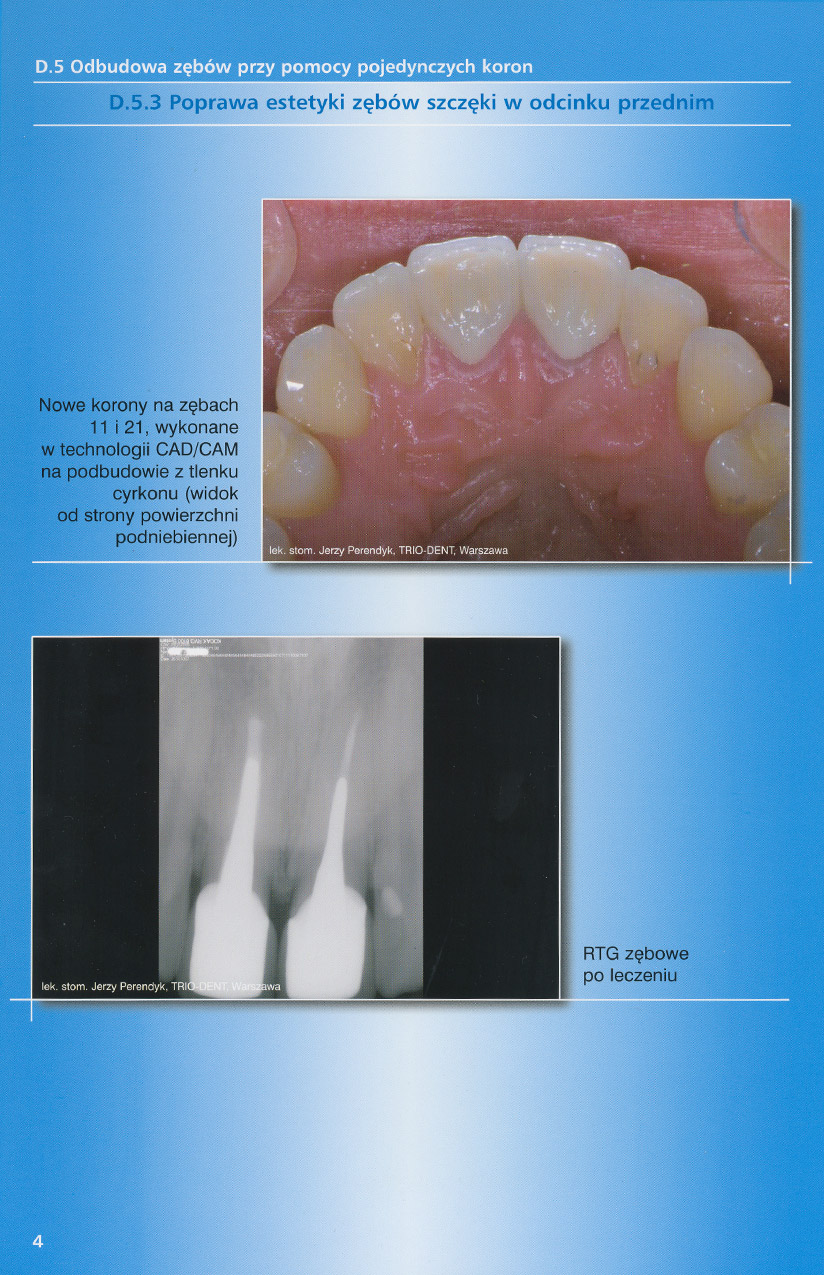

zobacz więcejGaleria przypadków klinicznych, obrazująca proces terapeutyczny od stanu wyjściowego aż do oddania ostatecznej pracy uzupełnienia brakującego uzębienia.